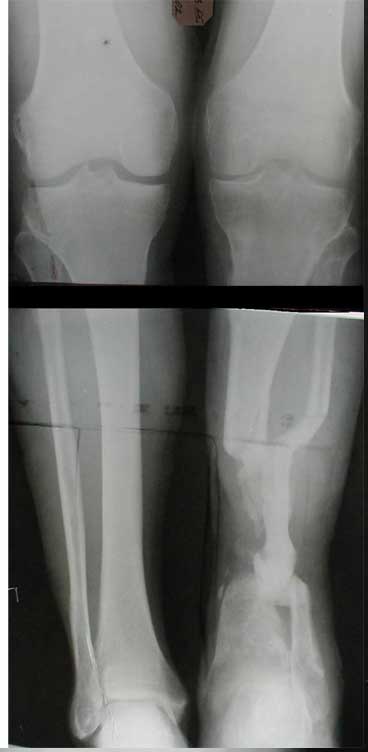

Лечил я его месяцев 8.

Малоберцовка полностью перестроилась, нога опороспособна.

При ходьбе на дальние расстояния пользуется тростью.

Осталась трофическая язва, периодически закрывается.